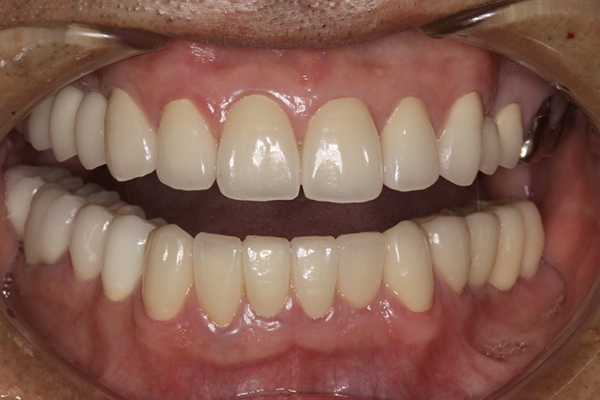

| 主訴 | 全体的にきれいにしたい |

|---|---|

| 治療内容 | 午前中に上下顎共に重度の歯周病、虫歯のため全ての歯を抜歯させていただき下顎はインプラントの土台を3本埋入し歯型を取り午後に上部構造(下顎全ての歯)を装着、上顎は一度総入れ歯を装着させていただきました。 治療が1日で完了しその日のうちに噛めるようになります。 |

| 治療期間 | 2回(1回目に資料取りをさせていただき2回目に下記の全ての治療をさせていただきました。) |

| 治療費 | 250万円 |

| 治療 リスク | 抜歯した部位などに関しては当日痛みが出ますので痛み止めなどを処方させていただきます |